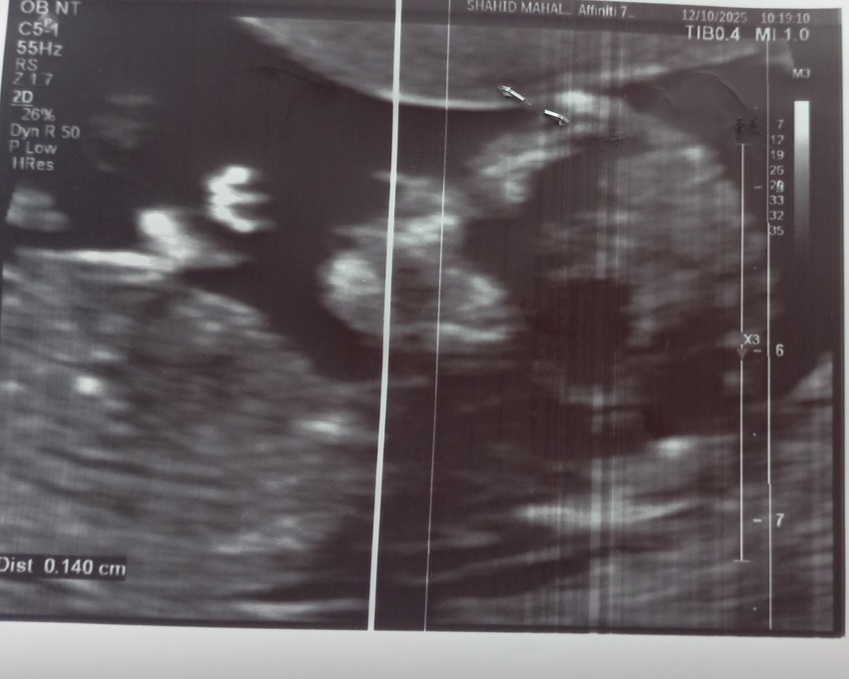

صدرابالام مدیر استارتر عضویت: 1400/11/03 تعداد پست: 873 عنوان تعیین جنسیت نی نی 43 بازدید | 3 پست سلام خانومامن امروز اومدم سونو ان تیضربان قلبو گفتن ۱۴۵ جنسیتشم نگفتنببینید میتونید کمکم کنید؟ 1404/09/19 | 12:23 0 نفر لایک کرده اند ... گزارش تاپیک نامناسب

صدرابالام مدیر استارتر عضویت: 1400/11/03 تعداد پست: 873 به منم جنسیتو نگفتنمنم باد نیستم تشخیص بدم خیلی دلم میخاد بدونمبچه اولمم پسرهآرزومه این یکی دختر باشهدادم هوش مصنویی اون دختر تشخیص داد ولی خب اعتمادیم نیست ک